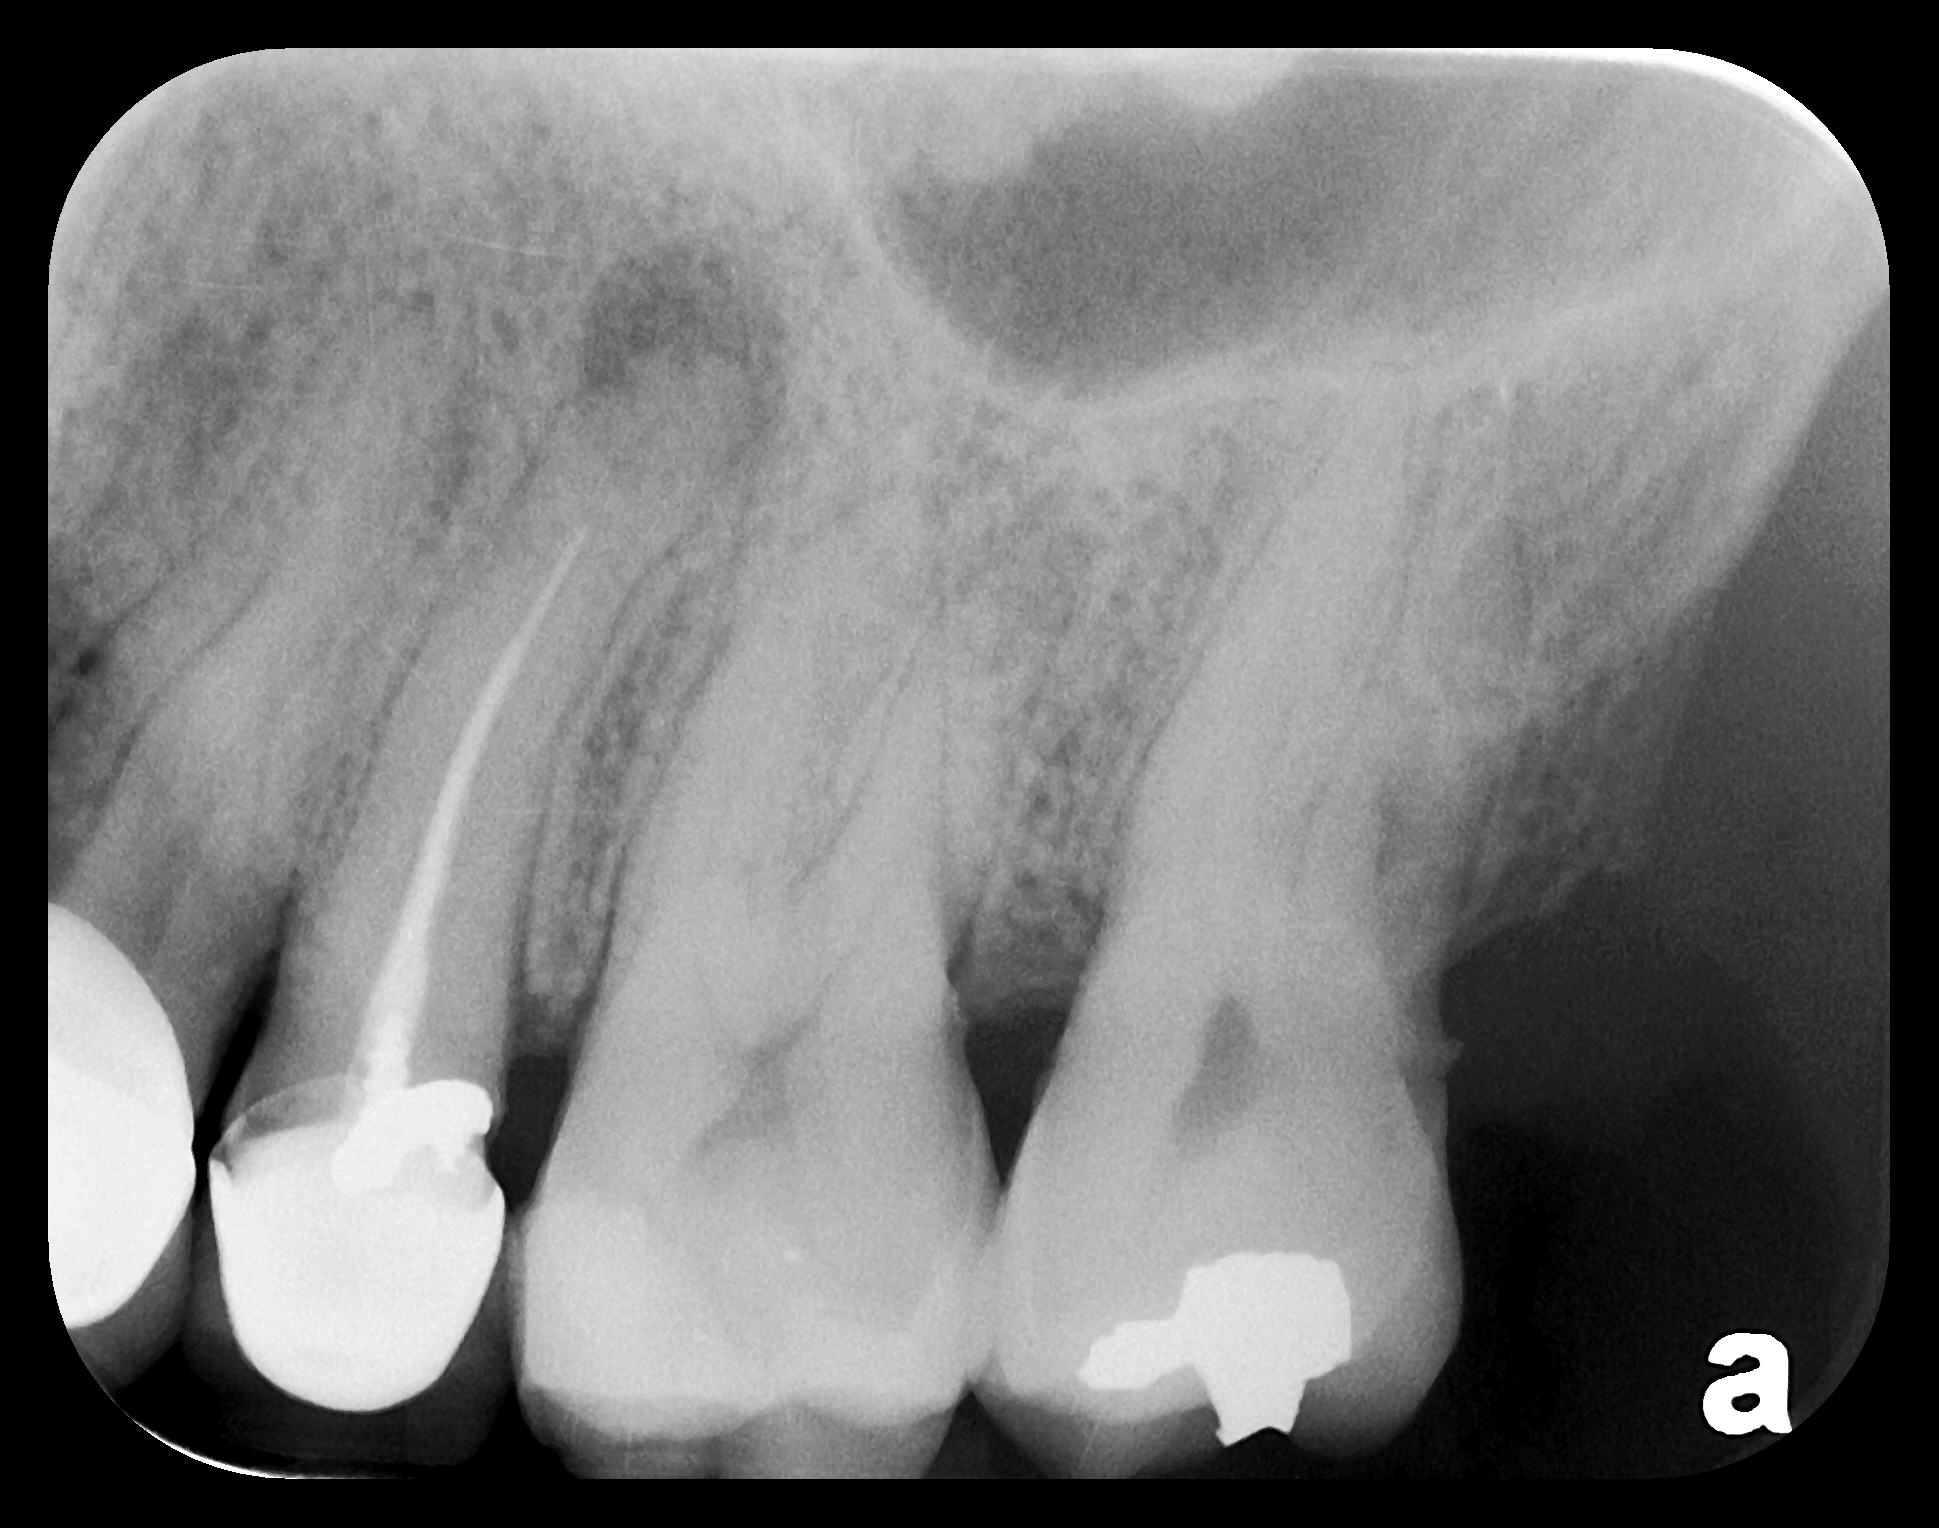

There are two specific types of DIDR sensor systems available to dentists in the marketplace: the hard-wired (HW) sensor and the photostimulable phosphor (PSP) sensor,1,2 also commonly known as phosphor "plates." A desirable feature common to both modalities is the ability to expose either bitewing (BW) or PA radiographic images. The BW radiograph (Figure 1) is usually considered more appropriate for caries detection, whereas the PA (Figure 2) is diagnostic for several different anatomic and pathologic issues.7

Fig 2. Left: PSP vertical PA radiograph of

maxillary bicuspid area demonstrating full root structure, several millimeters of bony anatomy beyond apices and maxillary sinus. Tooth No. 4 may be

traumatized as periodontal ligament is widened. Right: PSP horizontal PA radiograph of maxillary bicuspid area. Tooth No. 12 shows widened apical

periodontal ligament presumably caused by deep restorative filling. Some loss of supporting bone is evident interproximally, especially pronounced

between tooth Nos. 14 and 15.

Figure 2